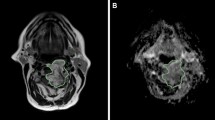

For the both datasets, the segmentation of the gross tumor volume (GTV) was performed by an expert radiologist on the DW-MRI computed with the lowest b value, where the tumor is the most visible. The preprocessing steps were performed using 3D Slicer [37].

First, small entity translations were applied to the ROIs, along both the x (medial-lateral) and y (antero-posterior) directions. By small entity, we mean translations of ± 10% of the length of the bounding box surrounding the ROI in the direction of interest (Fig. 1a). We will also refer to this type of translation as minimal entity translation. We assume the variability due to such transformations to be comparable to the ones that could appear in a multiple delineations test. In total, for each ROI, four minimal entity translations were applied (one positive and one negative for both the x and y directions) and thus four transformed ROIs were obtained. The radiomic features were computed on the four transformed ROIs and compared to the ones obtained with the original one (the one segmented by the radiologist). Radiomic features were then compared using two similarity indexes: (1) percentage variation and (2) intra-class correlation coefficient (ICC).

Example of translations applied to the regions of interest (ROIs). a Example of small entity translation in the y direction. b Example of maximal entity translation in the x direction. Continuous lines represent the contours of the original ROIs, while the dashed lines represent the contours of the modified ones

We repeat the above-described steps for increasing translation entities ranging from 10% (minimal entity translations) to 100% (maximal entity translations) with a step of 10%, and we computed the ICCmean and Diff%mean of the features for each translation, to evaluate how the similarity varies with the entity of the translations. In Fig. 1b, an example of maximal entity (± 100%) translation is represented. As it can be seen, this situation is far from the error range obtainable with multiple delineations. This type of transformation was used to evaluate discrimination capacity because, as previously stated, the underlying hypothesis is that if a feature remains constant independently on the entity of the translation, that feature is not going to be a good clinical descriptor.